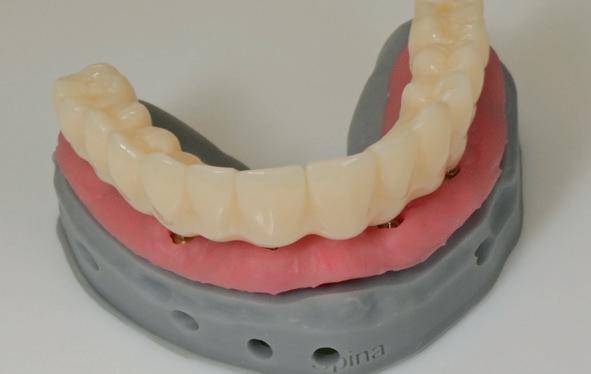

11. Tijdelijke PMMA-brug op model

Zitting 4 plaatsen PMMA brug & multi-unit abutments

Wanneer de tijdelijke brug retour komt, dienen eerst de healing abutments verwijderd te worden en de implantaten uitgespoeld te worden met Blue M spoelmiddel in een monoject. De brug paste niet direct op de interne verbindingen van de implantaten, omdat deze daarvoor niet parallel genoeg stonden, omdat de kaak in een curve liep. Daarom wordt over het algemeen gekozen voor multi-unit abutments die op de implantaten worden gedraaid. Hierdoor wordt de brug op coronaal hoger niveau geplaatst en door de multi-unit abutments wordt een open inzetrichting verkregen.

De PMMA tijdelijke brug werd direct op de multi-unit abutments geschroefd met kleine schroefjes. De schroefgaten van de brug werden afgesloten met teflontape en composiet. Indien nodig, kon er aan de PMMA brug de occlusie en articulatie geslepen worden. In deze casus was dat verder niet nodig. De

patiënt kon 2 maanden functioneren met de tijdelijke brug, waarna een kort consult werd gepland om te bespreken of hij tevreden was met de esthetiek en functie. Voor de patiënt hoefde niks veranderd te worden (afbeelding 11-14).